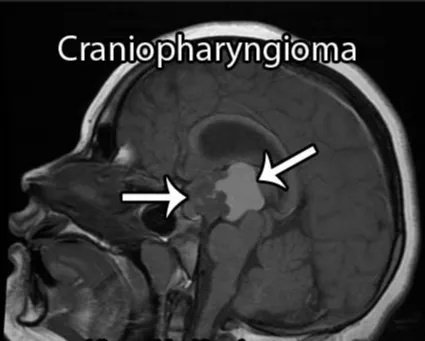

颅咽管瘤是一种良性肿瘤,虽然起源于垂体到下丘脑之间的很短一节垂体柄,但它能够生长成各种不同类型、质地、生长方向、各种各样的颅咽管瘤。不同解剖部位的颅咽管瘤可以是囊性的、实性的或囊实性的,还有部分肿瘤可能会存在一些钙化。它发生的主要部位在鞍区,也可以在鞍内、鞍上、鞍后、三脑室内部生长,可以侵袭到所有这些区域或部分这些区域。6-10岁儿童、26-30岁及41-45岁成人是颅咽管瘤的发病高峰年龄。男性一般多于女性。

颅咽管瘤可从垂体-下丘脑轴的任何一点发生并沿此轴发展,肿瘤可从位于蝶鞍到大脑的第三脑室,大约50%的肿瘤起源于第三脑室底水平的漏斗和/或灰结节区域,主要向第三脑室发展。患者可出现头痛、视力损害和由中枢性尿崩症导致的多饮多尿等症状,儿童可出现发育迟缓,成人可出现性功能障碍和下丘脑综合征(如体温调节紊乱、水电平衡紊乱)。

颅咽管瘤病变的起源及部位决定它周围的重要解剖结构,包括视神经、垂体柄、下丘脑、还有颈内动脉的分支,基底动脉的分支,尤其基底动脉、后交通动脉和大脑后动脉跟肿瘤的关系可能会非常密切,此外还有脑干等。视神经跟视力有关系,垂体柄跟内分泌有关系,下丘脑决定病人认知能力和术后内分泌功能,脑干则是人体的“生命中枢”,颈内动脉、基底动脉这些大血管总管人体血液运输,手术切除过程中一旦损伤这些重要结构,可能导致灾难性、不可逆的神经功能损伤。